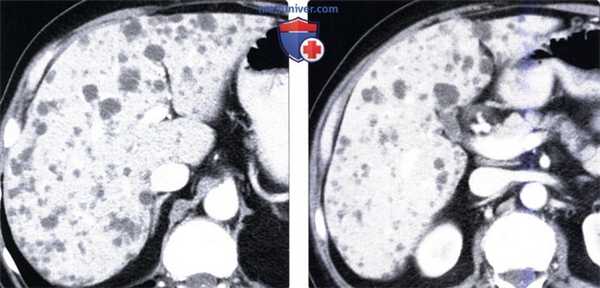

(Слева) На аксиальной КТ с контрастным усилением визуализируются множественные мелкие (меньше 15 мм в поперечнике) очаги с плотностью, близкой к плотности воды, диффузно разбросанные по всей паренхиме печени. Эти очаги остаются стабильными, не обусловливают наличие симптоматики, и вероятно представляют собой билиарные гамартомы. У пациента не обнаружено признаков поликистозной болезни.

(Справа) На аксиальной КТ с контрастным усилением у этого же пациента также визуализируются билиарные гамартомы. Если в анамнезе нет указаний на первичную злокачественную опухоль, в большинстве случаев необходимость в биопсии отсутствует.